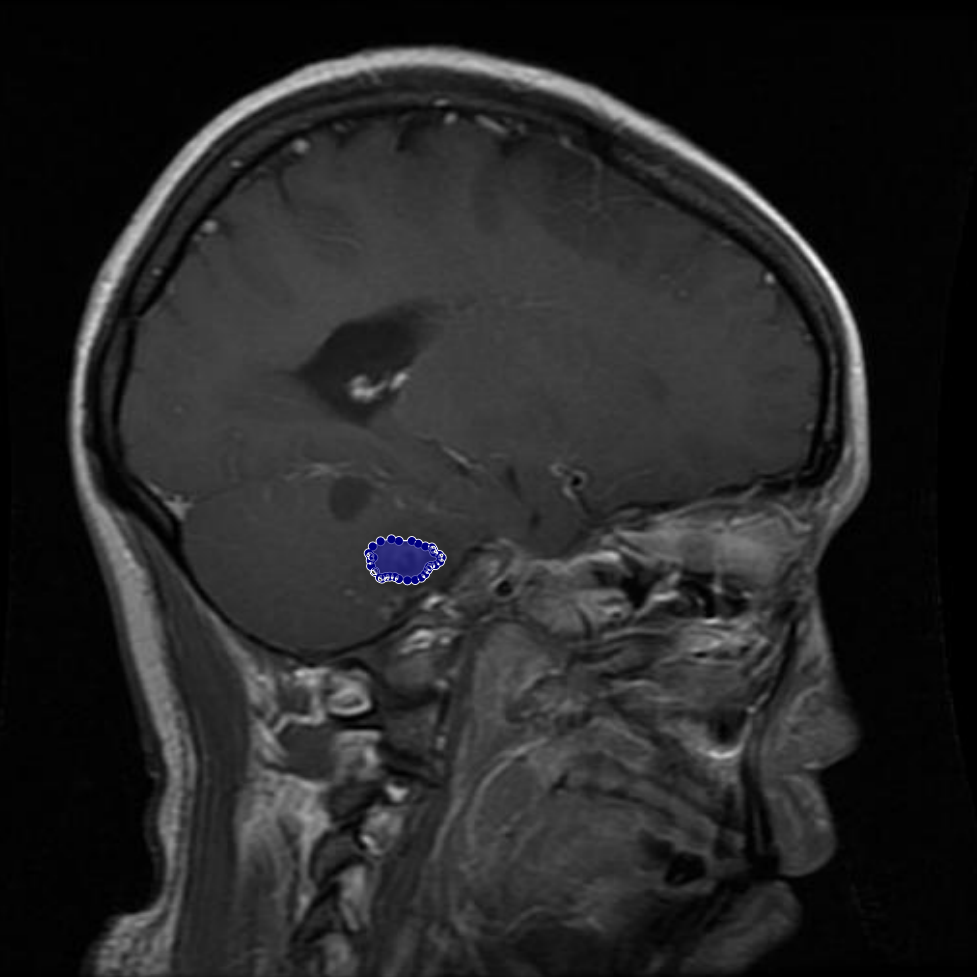

In some cases, regions initially annotated as tumors were later identified by physician and radiologist as non-tumorous. These corrections were essential to avoid false positives that could mislead model training. An example of such a case is shown in Figure 5, where an area initially believed to be a tumor was excluded from the final annotation after expert review.

Figure 5: Samples of whole-region misannotations. The red area indicates regions that were initially marked as tumors but were identified by radiologist and physician as non-tumorous.